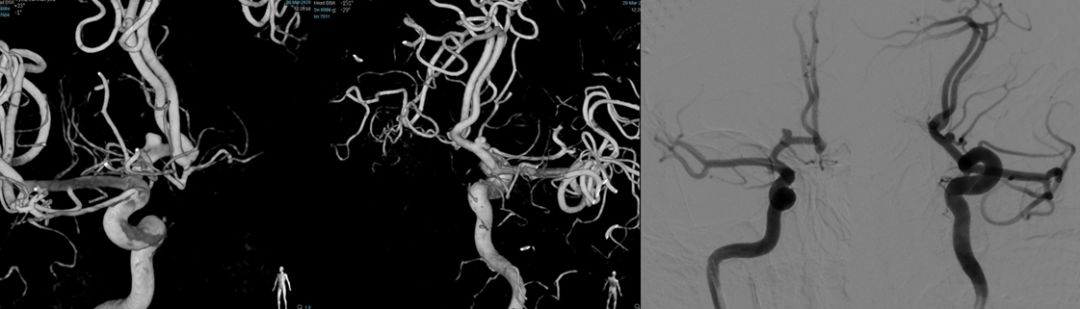

图1 术前造影显示右侧颈内动脉A1段动脉瘤,伴子瘤样改变,返动脉发自瘤体

图3 三维旋转见右侧A1、A2角度较大